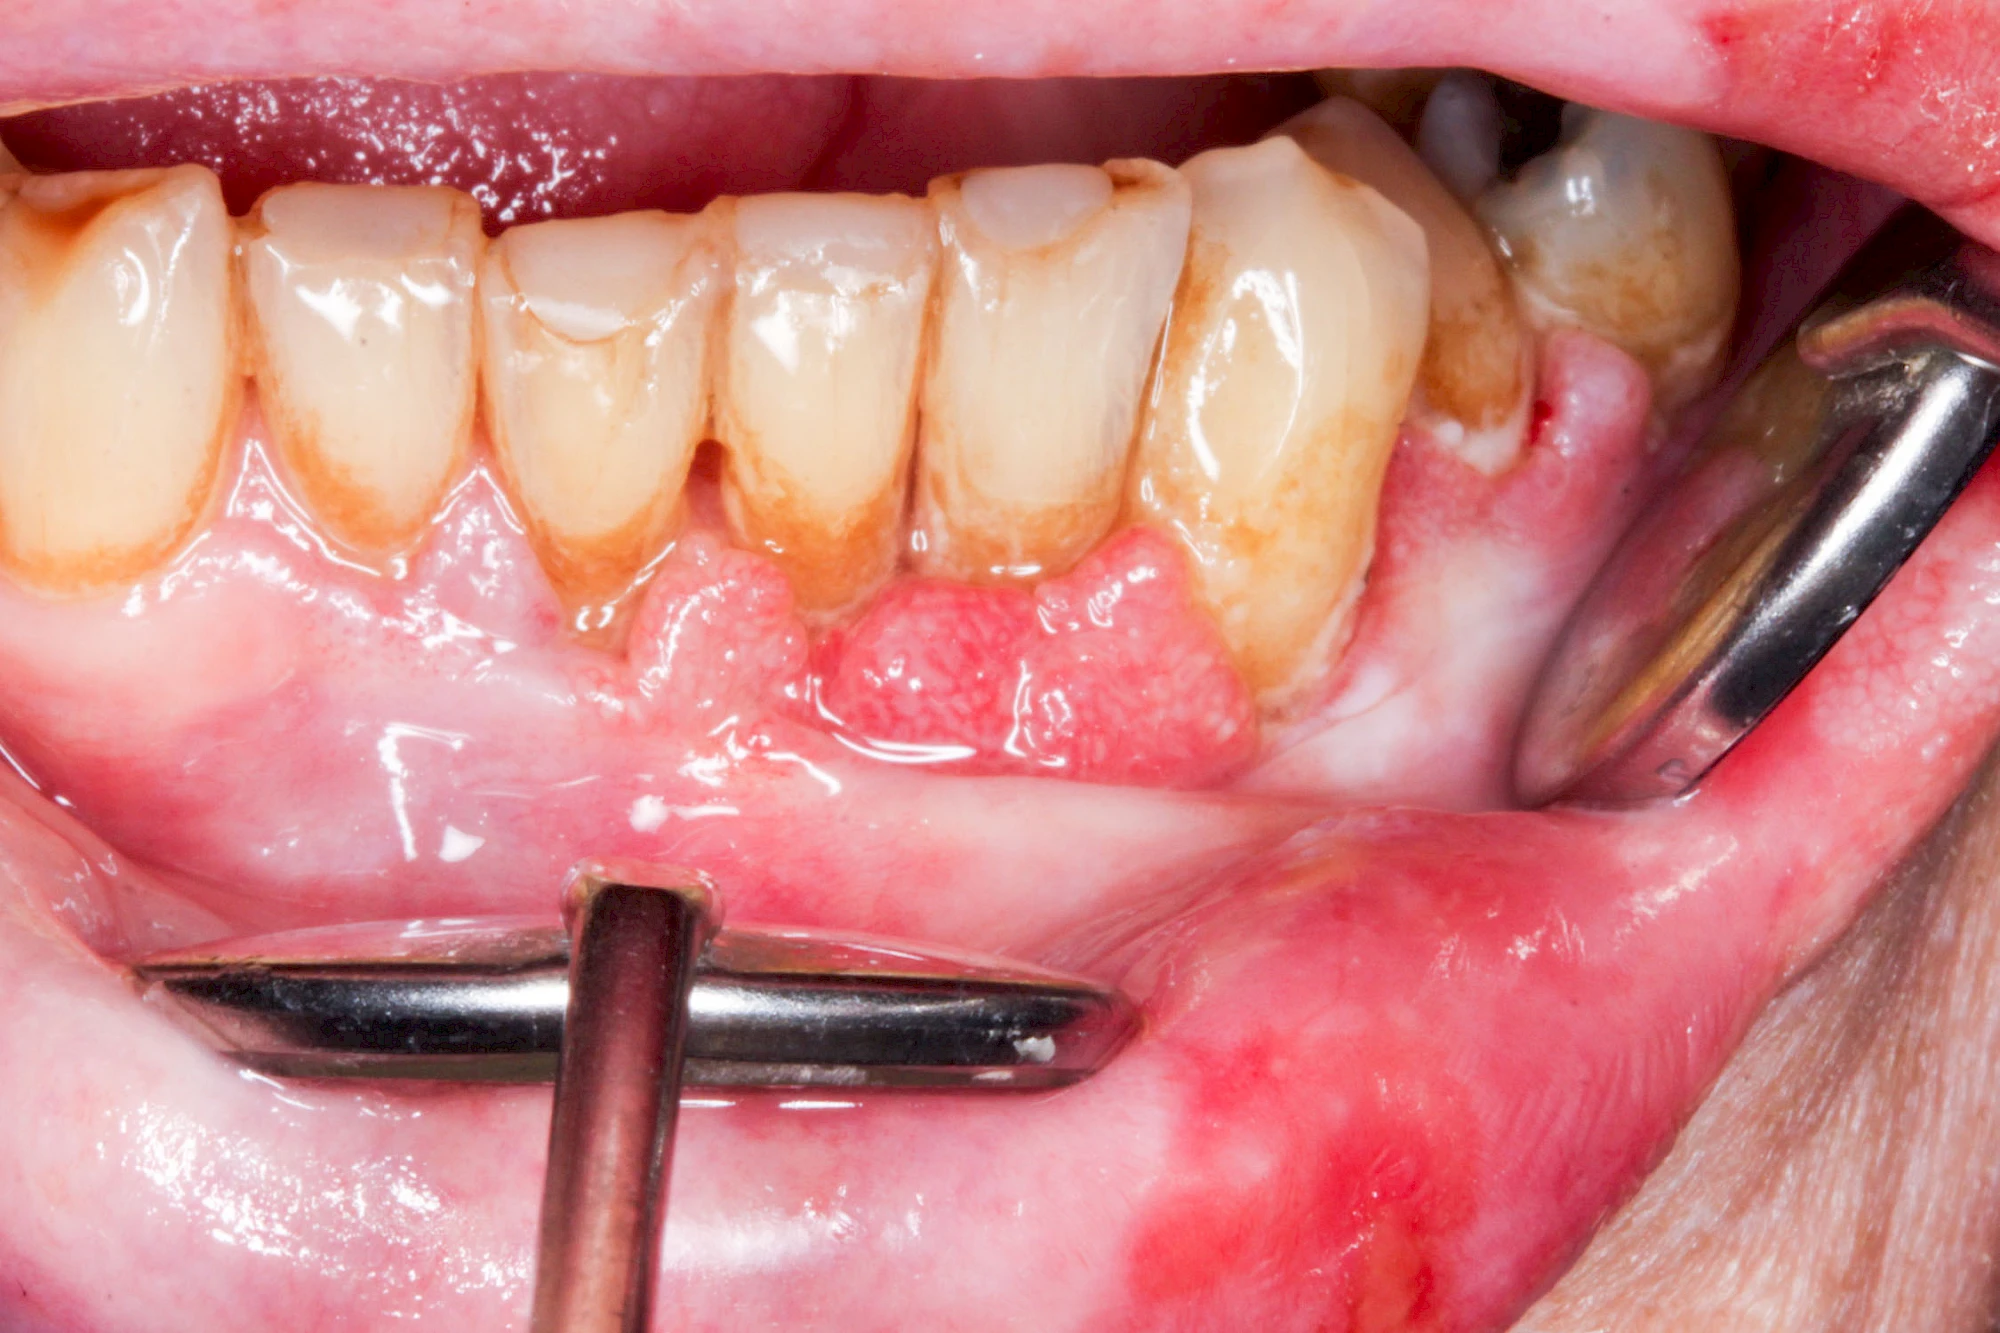

Sonderform: Wucherung

Epulis

Diese Vermehrung von Bindegewebe im Bereich des Zahnfleisches kann auf folgende Ursachen zurückgeführt werden:

- Nebenwirkung von Medikamenten: Immunsuppressiva (Cyclosporin A), Antihypertonika (Kalziumantagonisten/Kalziumkanalblocker: Nifedipin, Amlodipin sowie Diltiazem, Verapamil) und Antiepileptika (Phenytoin)

- Hormonschwankung im Rahmen der Schwangerschaft (Schwangerschaftsepulis)

Vakatwucherung

Diese Vermehrung von Bindegewebe in einem frei gewordenen Raum ist eine Sonderform der Anpassungsreaktion menschlicher Zellen und wird als Vakatwucherung bezeichnet.

Früher wurden im Unterkiefer mitunter Brücken zum Ersatz fehlender Zähne als sogenannte "Schwebebrücken" gestaltet. Die Idee dabei war, dass man die Brücke insgesamt besser reinigen kann. Allerdings war das für die Patienten mitunter irritierend für die Zunge und vor allem beim Essen gewöhnungsbedürftig. Teilweise haben sich hier reaktiv Vakatwucherungen der Kieferkammschleimhaut gebildet und den Raum unter der Brücke wieder verschlossen.